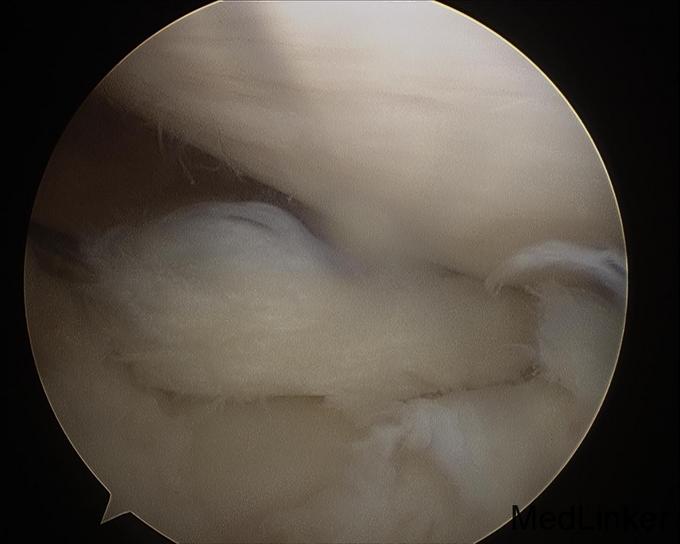

随访:患者术后扶拐行走2周。2周后活动度恢复正常,亦恢复正常行走。 讨论:该患者为前交叉韧带自体肌腱重建术后9年,难得有机会进行second look。术中发现重建韧带形态完整,但纤维松散,术前查体亦有松弛现象。术中予以紧缩处理后,术后松弛度明显改善。